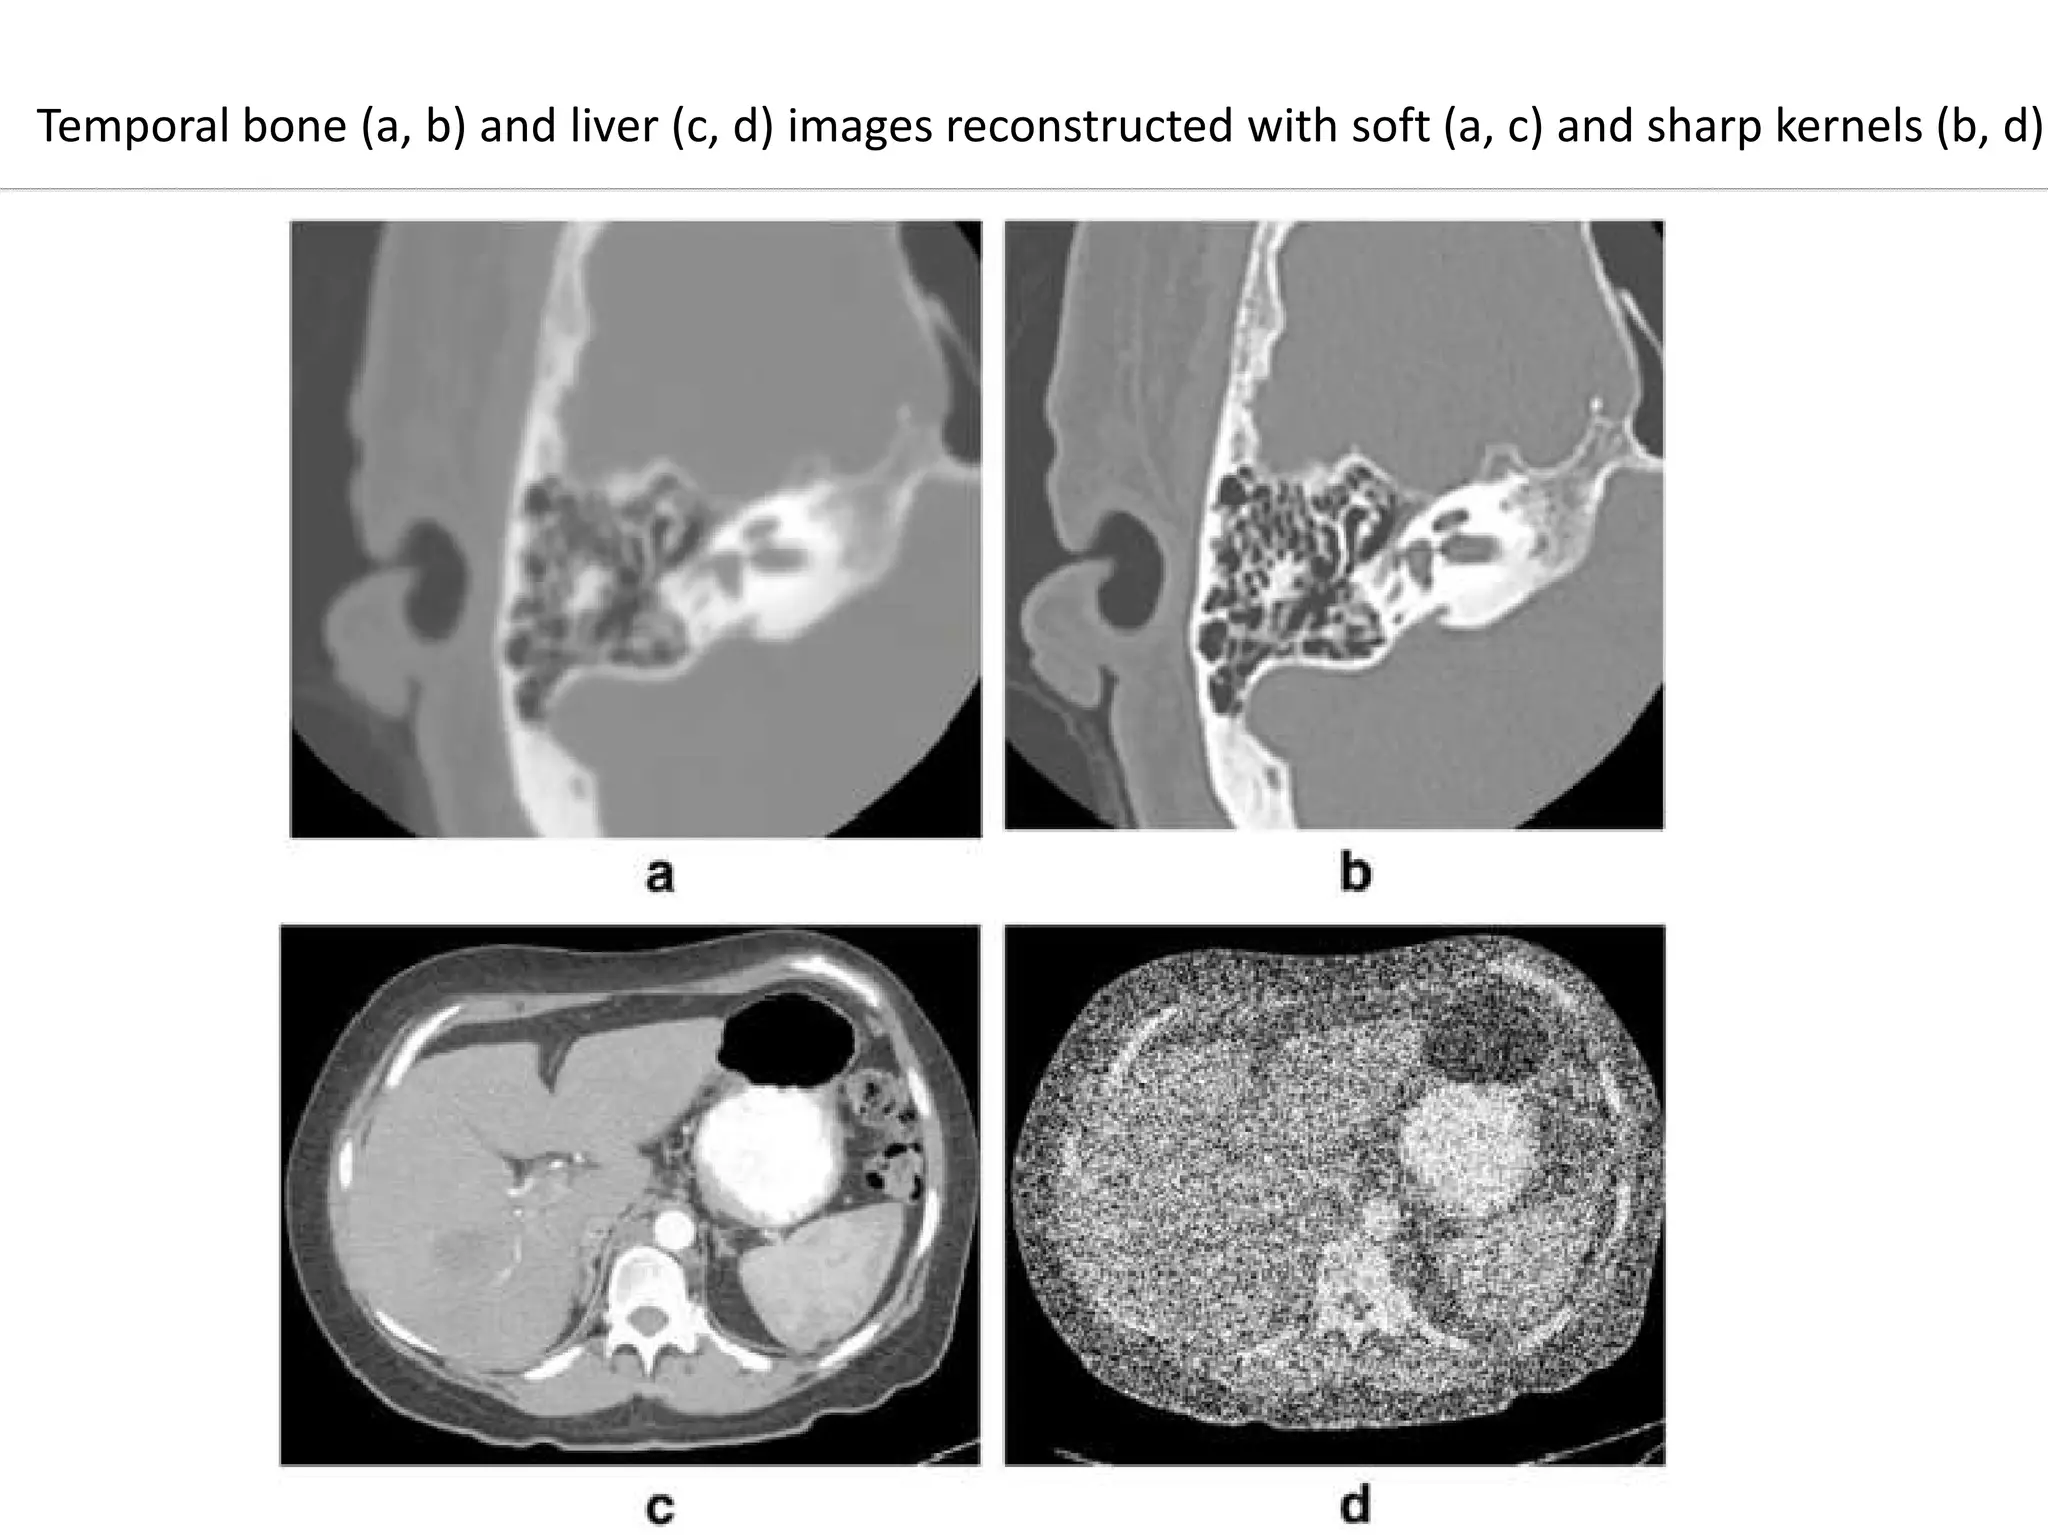

• For example, smooth kernels are usually used in brain

exams or liver tumor assessment to reduce image

noise and enhance low contrast detectability, whereas

sharper kernels are usually used in exams to assess

bony structures due to the clinical requirement of

better spatial resolution.

• Conversely, some filters accentuate the difference between

neighboring pixels to optimize spatial resolution, but must

make sacrifices in low-contrast resolution.

• These latter filters are most often used when there are

great extremes of tissue density and when optimal low-

contrast resolution is not necessary. An example is images

of the internal auditory canal in which the tiny bones of theof the internal auditory canal in which the tiny bones of the

inner ear are displayed; the tissue densities of interest are

limited to bone or air, with high inherent tissue contrast so

the image can be reconstructed for spatial rather than

contrast fidelity .

• These types of high-contrast reconstruction algorithms are

often called bone or detail filters.

Temporal bone (a, b) and liver (c, d) images reconstructed with soft (a, c) and sharp kernels (b, d)